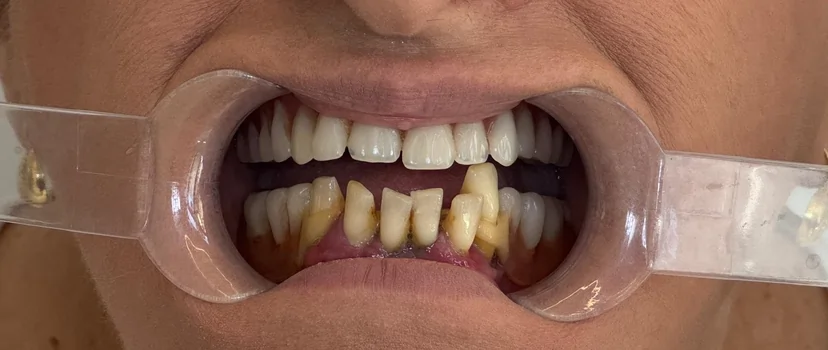

Transformări Reale

Imaginile vorbesc mai bine decât cuvintele. Descoperă rezultatele obținute în clinica noastră.